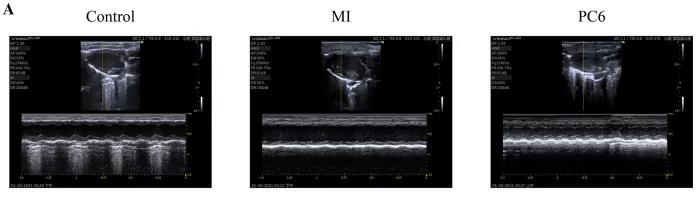

成年雄性C57BL/6雄性小鼠隨機(jī)分為對照組、MI組和PC6組。MI組小鼠為通過結(jié)扎冠狀動脈左前降支(LAD)形成MI模型,PC6組在造模完成后,針刺內(nèi)關(guān)穴治療5天后取材。經(jīng)胸超聲心動圖評估MI手術(shù)前后小鼠心功能情況,并進(jìn)行血清心肌酶和炎癥細(xì)胞因子的測定,之后三組樣本各取3個重復(fù),共9個樣本進(jìn)行ONT全長轉(zhuǎn)錄組測序。

為了探討針刺PC6穴對心肌損傷的影響,作者首先評估了心功能和梗死面積。超聲心動圖結(jié)果顯示MI組的EF(ejection fraction)和FS(fractional shortening)均較對照組明顯降低。PC6穴位治療后,EF和FS均增加。針刺治療5天后, 采用TTC染色檢測梗死面積。結(jié)果顯示,針刺治療顯著減小心肌損傷的大小。采用ELISA法測定反映急性心肌損傷的心肌特異性血清酶,包括心肌肌鈣蛋白T (cTnT)和心肌肌鈣蛋白I (cTnI)的水平。結(jié)果表明,心肌梗死術(shù)后cTnT和cTnI水平升高,針刺可顯著降低血清酶水平。